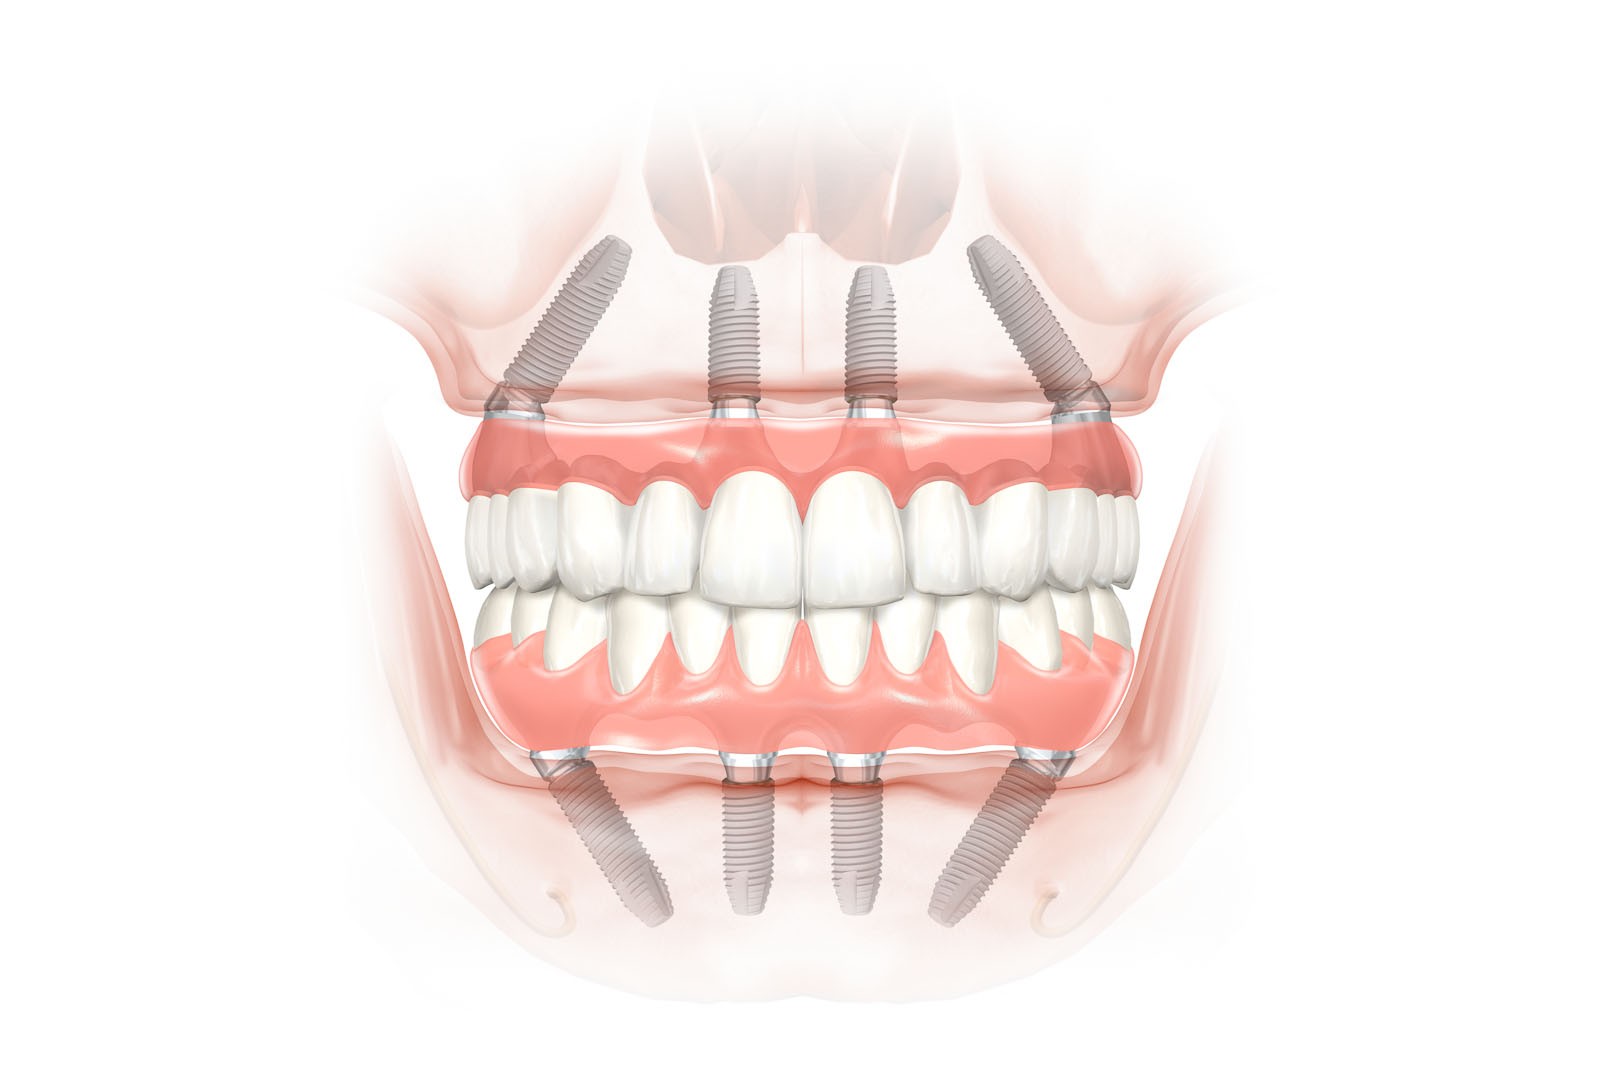

- Procedury All-on-4 – opatentowane rozwiązanie rekonstrukcji całego uzębienia szczęk lub żuchwy mocowane tylko na 4 implantach zamocowanych, w tym 2 mocowanych skośnie

- Procedury All-on-6 – rozwiązanie pełnej rekonstrukcji uzębienia mocowane na 6 implantach

- Zabiegi implantologiczne połączone jednoetapowo z natychmiastowym obciążeniem koronami lub protezami

- Procedury natychmiastowego obciążenia mostami protetycznymi mocowanymi bezpośrednio po wszczepieniu implantów dla systemowych rozwiązań przy bezzębiu